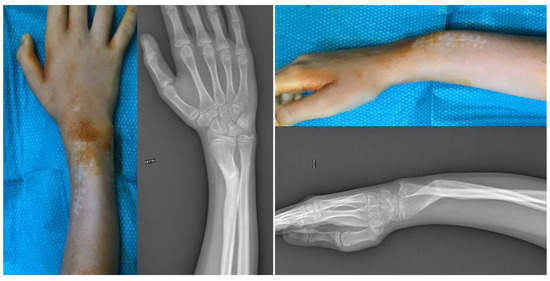

2.1. Case Presentation

2.4. Surgical Treatment